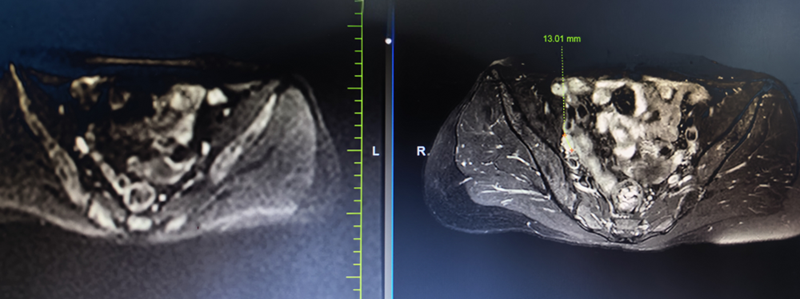

磁共振:右侧盆腔淋巴结转移。

宫颈鳞状细胞癌IIIC1r期。

宫颈鳞状细胞癌IIB期。